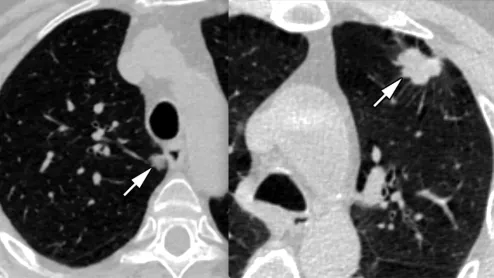

Examples of two lung cancers that were caught using low dose CT lung screening. Image from RSNA

The ACR said a recent reimbursement rule change for low-dose computed tomography (CT) lung screen scans will help open up screening to more patients.